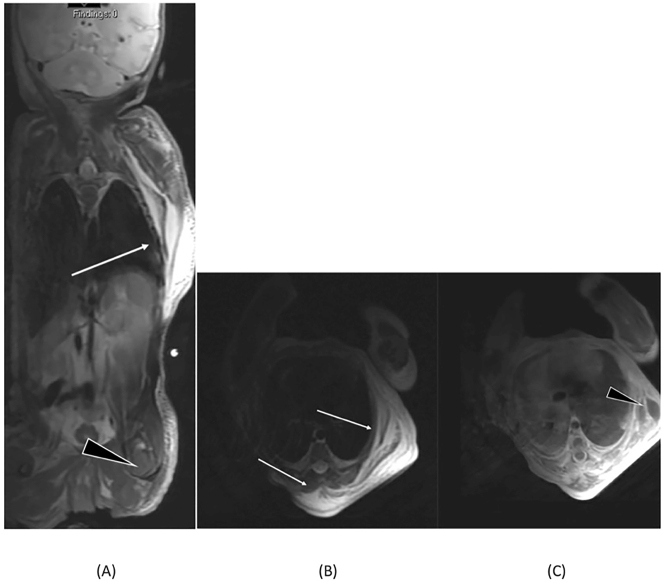

Case presentation: A 32 weeks 6 days pregnant Caucasian woman was admitted after premature prelabor rupture of membranes (PPROM). Fetal ultrasound showed no abnormalities, the infant was born by a caesarean section. The delivery was complicated by the infant's transverse position. A female infant was born with a large left-sided dorsal soft tissue mass at the thoracic level with elastic consistency, and multiple skin lacerations. A broad differential diagnosis was made. Additional imaging was suggestive for a posttraumatic swelling due to transverse position during birth. The mass decreased and disappeared over three days.